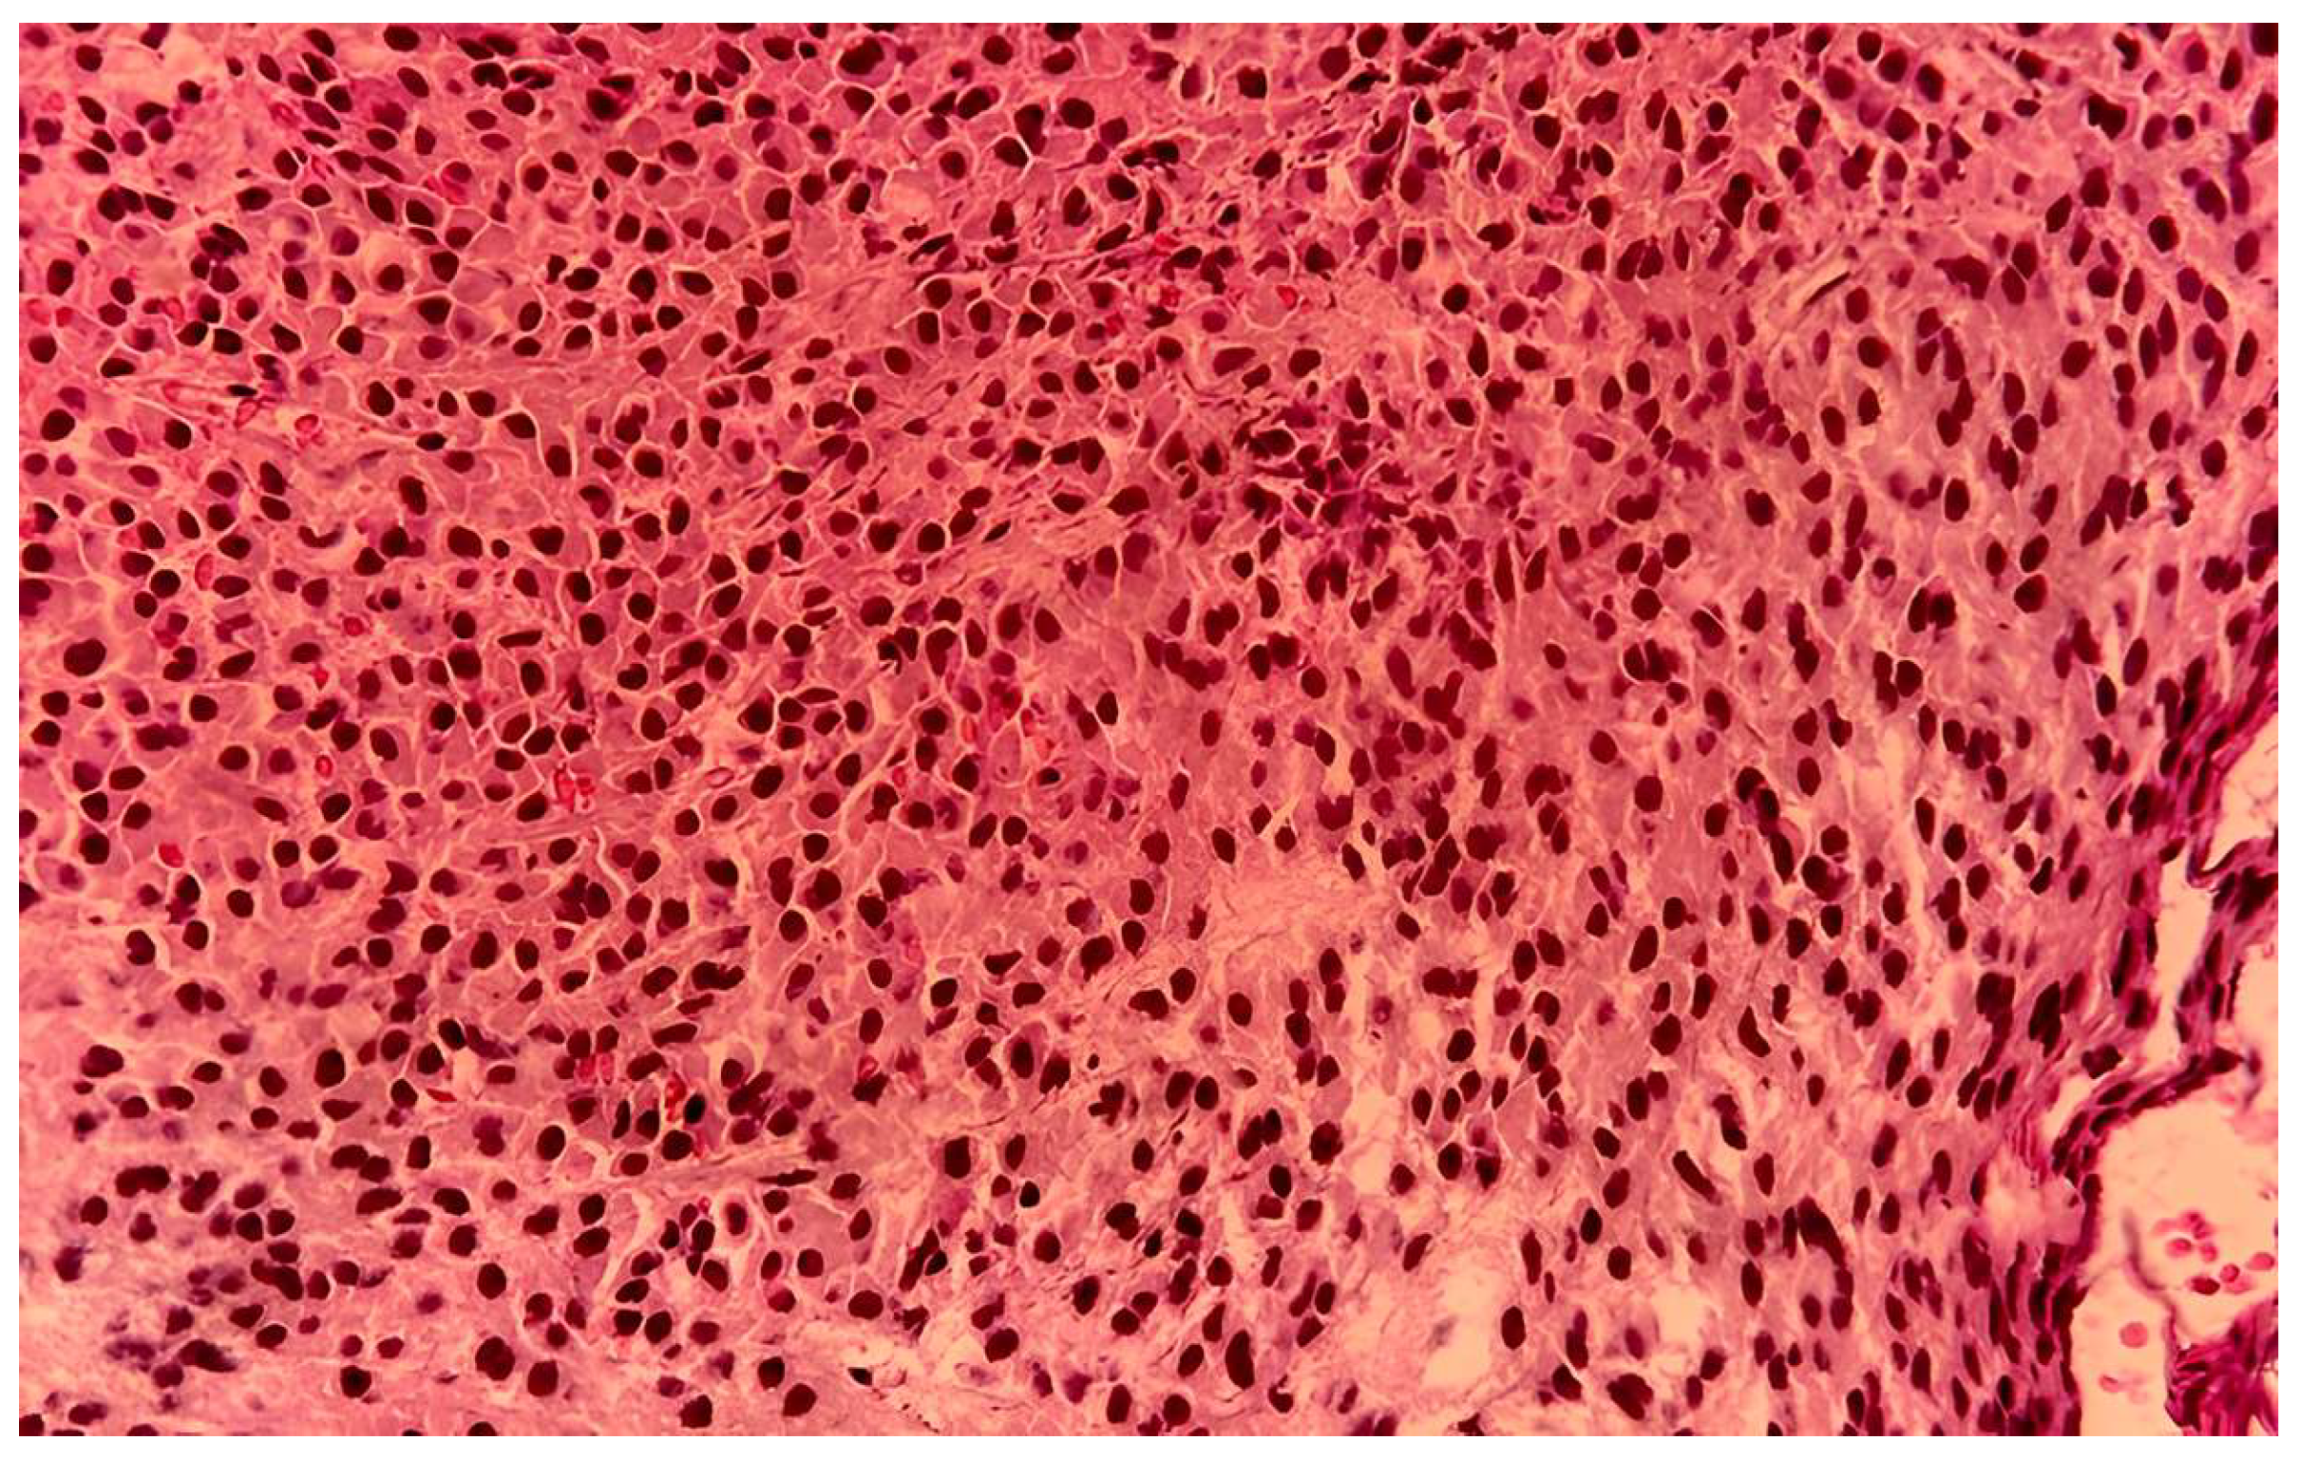

| Histopathology | Plasmacytoid cells, hemorrhage | Plasmacytoid cells, necrosis | Compact eosinophilic cells |

| Immunohistochemistry | CD38+, CD138+ | CD79a+, CD138+, CD56+ | CD138+ |